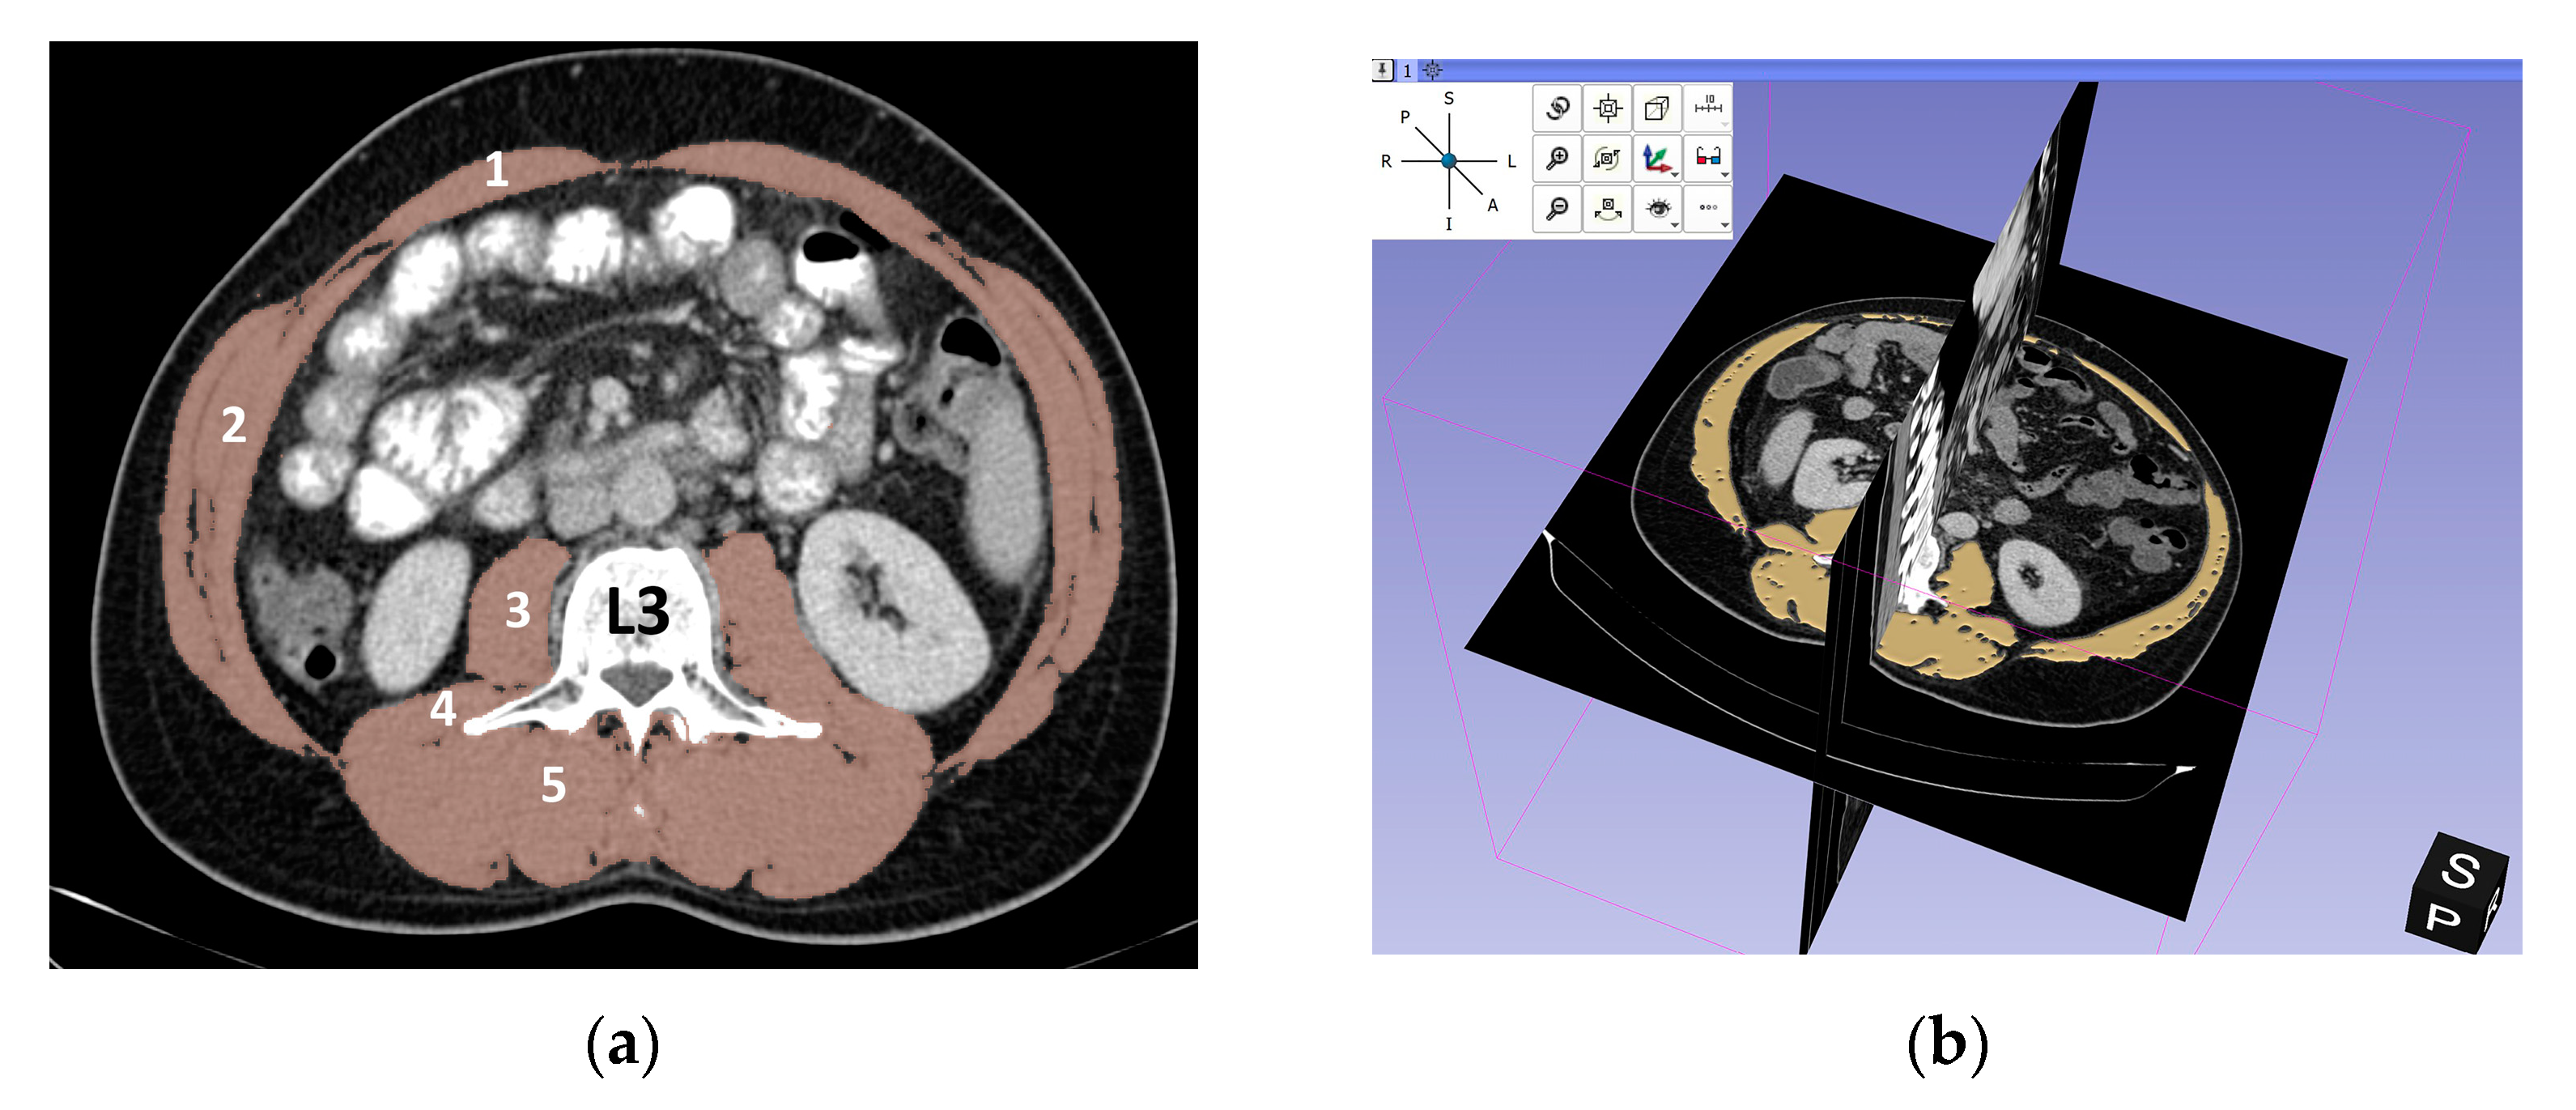

2.3. Assessment of L3-SMI (Skeletal Muscle Index)